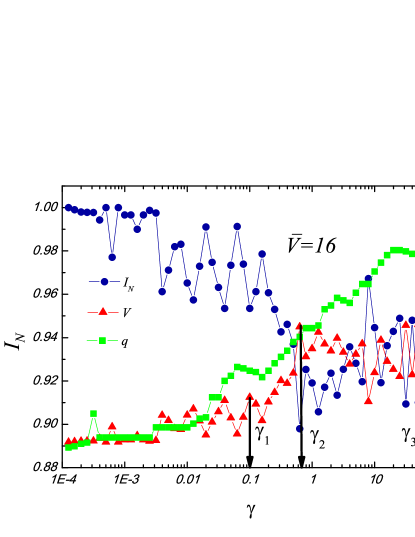

XI.1 Brain Image

XI.1.1 Unweighted graphs

We start the review of the results of our methods by analyzing an unweighted graph (Eq. (1)) for the grey-scale brain image as shown in Fig. 5. We will assign edges between pixels only if the intensity difference is less than the threshold as denoted in panel (a) of Fig. 5. The algorithm uses Eq. (1) to solve for a range of resolution parameters in the interval . In the particular case in Fig. 5, and . There are two more input parameters that are needed in our algorithm: the number of independent replicas that will be solved at each tested resolution and the number of trials per replica . We use and in Fig. 5 respectively.

As noted earlier (see Section V), for each replica, we select the lowest energy solution among the trials. The replicas are generated by reordering the “symmetric” initialized state of one node per community. We then use the information based measures (i.e., or ) to determine the multiresolution structure.

The plots of , and as a function of in Fig. 5 exhibit non-trivial behaviors. Extrema in and correspond to jumps in the number of communities . In the low region, i.e., , the number of communities is stable. However, when , the number of communities sharply increase. This indicates that the structure changes rapidly as the resolution varies. There are three prominent peaks in the (variation of information) curve. We show the corresponding images at these resolutions, that is in panel(b) in Fig. 5. These corresponding segmented images show more and more sophisticated structures. The lower right image at a resolution of shows the information in detail. Different colors in the image correspond to different clusters. There are, at least, five contours surrounding the tumor, that denote the degree by which the tissue was pushed by the tumor. The lower left image at the resolution is less detailed than the one on the right. Nevertheless, it retains the details surrounding the tumor. If we further decrease , the upper right image at the resolution will not keep the details of the tumor boundary, only the rough location of the tumor. Thus, neither too large nor too small resolutions are appropriate for tumor detection in this image. The resolution around is the most suitable in this case. This is in accord with our general found maxim in Section IX concerning a value of . We re-iterate that, in general, the optimal value of is found by Eq.(21) (an example of which is manifest in the information theory plateaus discussed in Section VII.2). In Section XI.7, we will discuss, in depth, how the optimal values of may be determined in (weighted) example systems.